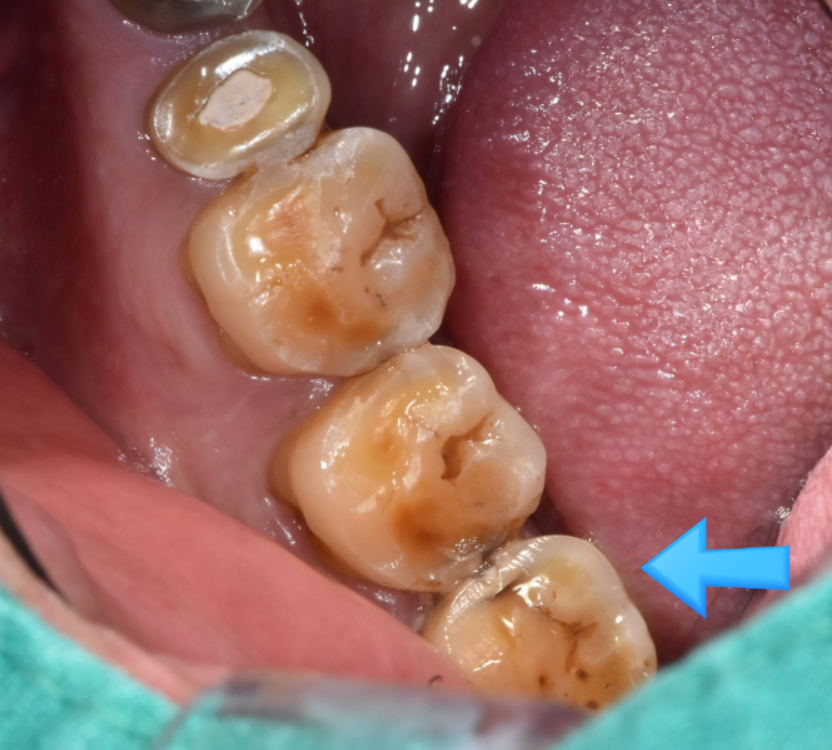

하남 미사 치과에

윗니 치아가 1개 빠져서 내원하신 환자분

이가 빠지고 나서 바로 치료를 하면

움직임이 없지만

사정에 따라 뒤늦게 치료를 해야할 때가 있습니다.